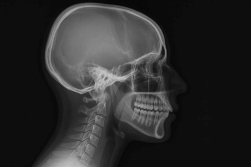

Des luxations discales avec ou sans impact occlusal

Une luxation discale est un déplacement anormal du disque articulaire de l'ATM.

Elle est dite réductible quand le disque peut reprendre sa place (généralement en fermant la bouche), et irréductible dans le cas contraire.

Une luxation réductible provoque ou non un bruit articulaire lors des mouvements, n'entraîne pas forcément une gêne, et ne modifie pas l'occlusion des dents.

En cas de luxation non réductible, le disque ne peut pas reprendre sa place, même avec une manipulation manuelle. Il y a une gêne, des douleurs, une restriction de l'amplitude d'ouverture et une modification de calage entre les dents, donc de l'occlusion.

La position de relation centrée

La position de relation centrée correspond à une position spécifique de la mâchoire inférieure par rapport à la mâchoire supérieure. Il s'agit de la position où l'articulation temporo-mandibulaire (ATM) est dans son état le plus stable et le plus équilibré, sans tension musculaire ou sollicitation excessive des structures articulaires. C'est une position dans laquelle le patient peut trouver le repos.